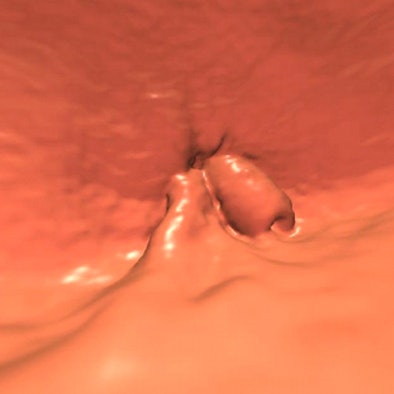

"We looked at the VC that was performed on him, and there really wasn't a whole lot to see -- a questionable lesion in a difficult area sort of near where the rectal catheter is," Pooler said. "We looked at it on a few different views."

![]() |

| 65-year-old patient developed a low rectal adenocarcinoma, stage II (T3, N0), three years after a negative screening VC; original lesion seen in endoluminal view above. Image courtesy of Dr. Dustin Pooler and Dr. Perry Pickhardt. |